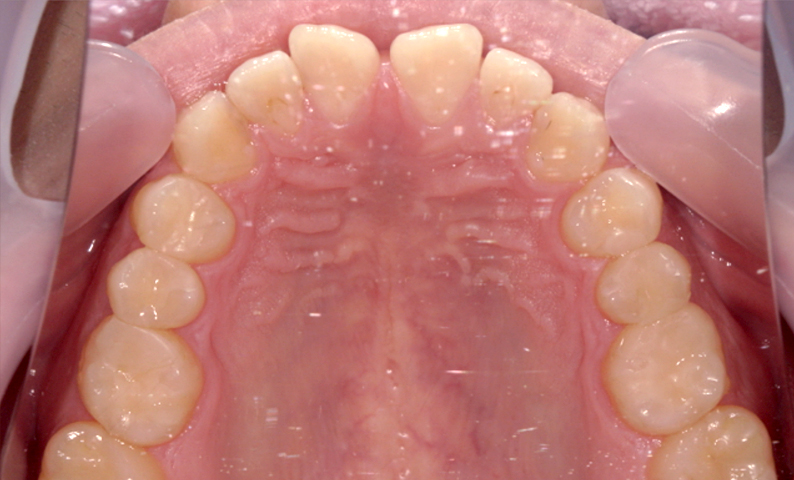

| 治療前 | 治療後 |

|---|---|

|